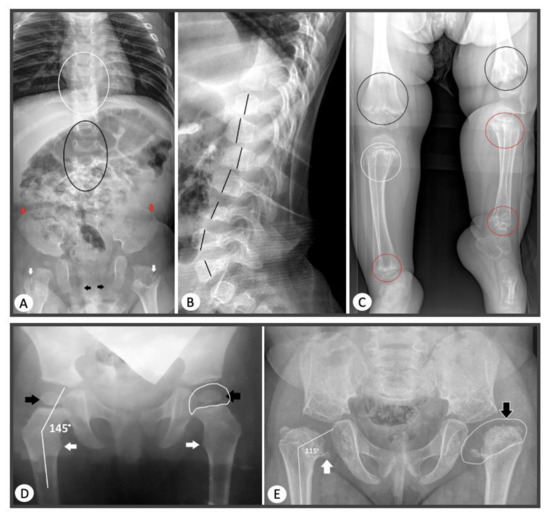

The phenotypes of patients with the most common glycine substitutions varied from classical SEDC to mild forms of SED. In two probands with a similar course of SEDC, the glycine to serine substitution was found at a hotspot: c.1510G>A (p.Gly504Ser) [15]. In three other probands with severe SEDC, a previously undescribed substitution of glycine to serine was found: c.2671G>A (p.Gly891Ser). In addition, there was a polymorphism of clinical manifestations in two probands with a similar variant, where a substitution of glycine to serine at the 546 nucleotide position was detected. One of the patients had typical signs of SEMD and another one had a mild phenotype of SED with normal growth, as confirmed by the data of Chen J. et al. [27], where an interfamily clinical polymorphism was identified in patients with this pathogenic variant. In two patients with newly identified substitutions leading to glycine substitution: c.1348G>C (p.Gly450Arg) and c.3554G>A (p.Gly1185Glu), radiography revealed the presence of enchondroma-like changes in metaphyses, anisospondylia, limb length discrepancy, and abnormal ossification pattern of the pubic bones which are typical for dyspondyloenchondromatosis (Figure 4).

Figure 4.

Radiological signs of COL2A1-skeletal dysplasia in probands from our sample. (A) AP radiograph of thoracolumbar spine, pelvis, and hips of the patient with dysspondyloenchondromatosis. Anisospondyly and mild wedge-shape vertebral bodies of the thoracic (white circle) and lumbar (black circle) spine; lacy iliac crests (red arrows); deficient ossification of the pubic bones (black arrows); chondromatous lesions of the femoral necks (white arrows). (B) Lateral radiograph of thoracolumbar spine of the patient with dysspondyloenchondromatosis. Anisospondyly of the thoracic and lumbar spine (the heights of the vertebral bodies marked with the black lines). (C) Radiograph of both legs of the patient with dysspondyloenchondromatosis. Extensive chondromatous lesions of the metaphyses of the distal femora (black circles), proximal (white circles), and distal (red circles) tibiae and fibulae; remarkable length discrepancy on the lower legs. (D) AP radiograph of the hips of the patient with mild phenotype. Coxa valga (neck-shaft angle 145°, normal length of the femoral necks), normal ossification of the femoral head and neck (black arrows), and lesser trochanter (white arrows); normal shape of the femoral head (white line depicts presumed contour of the cartilaginous femoral head). (E) AP radiograph of the hips of the patient with severe phenotype. Hypoplastic iliac wings, coxa vara et breva (neck-shaft angle 115°, short femoral neck), abnormal ossification of the femoral head and neck (black arrow), and lesser trochanter (white arrow); abnormal shape of the femoral head-coxa plana (white line depicts presumed contour of the cartilaginous femoral head).